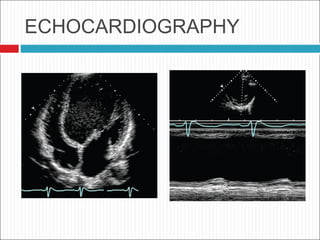

ECHOCARDIOGRAPHY.

 Cornerstone in the evaluation and

management

 LVEDD are usually greater than 60 mm

 Global hypokinesia

 Decreased EF and FS

 Associated ds

ECHOCARDIOGRAPHY